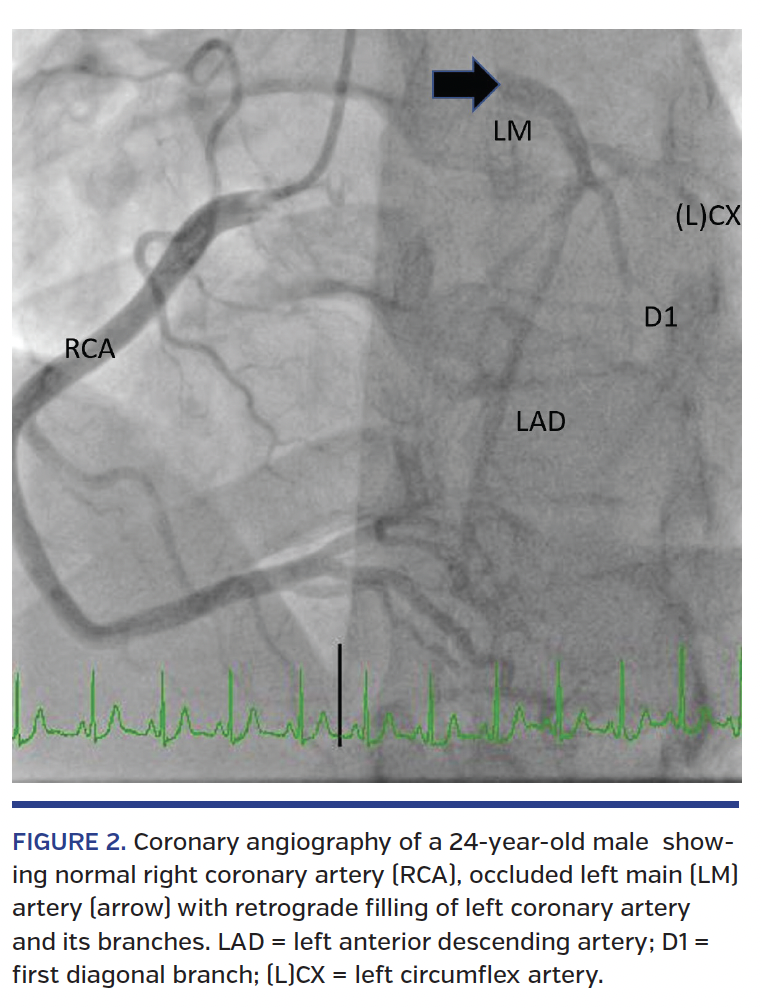

We report the case of a 24-year-old male who presented to hospital following syncope with electrocardiographic changes and was found to have LMCA occlusion requiring emergent coronary artery bypass grafting. His only risk factor for vascular disease was smoking 1 or 2 cigarettes a day. The electrocardiogram showed diffuse ST depression across all leads, except aVR, for which there was ST elevation (Figure 1). He was taken for urgent coronary angiogram, which showed occluded LMCA that filled retrogradely from the right coronary artery (Figure 2 and Video 1). He proceeded to emergent coronary artery bypass surgery. Postoperative course was unremarkable and the patient was discharged 12 days later.